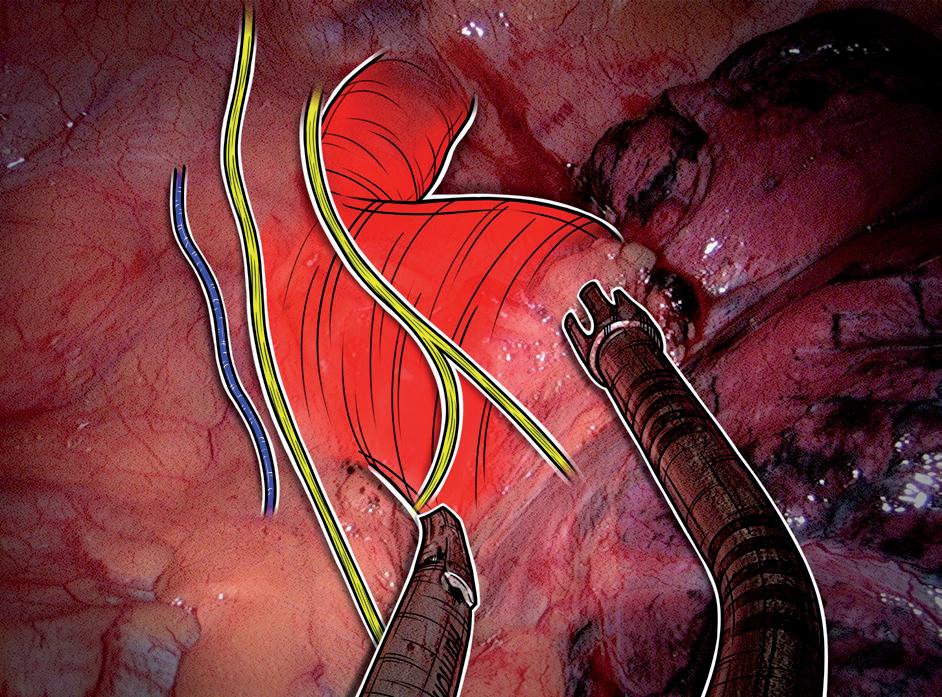

obr. 7.8 Nervus laryngeus recurrens sinister bývá při lymfadenektomii uzlin na aortálním oblouku a v aortálním okně (stanice 6, 5 a případně 4L) vystaven vyššímu riziku poranění než zvratný nerv vpravo. Mohou být poraněna jeho vlákna v průběhu levostranného vagu, stejně jako jeho samostatný průběh pod aortálním obloukem. Levý rekurent se přiklání k průdušnici a stoupá vzhůru po její levé ploše. Z tohoto důvodu může být poraněn zde i při mediastinoskopii. Na fotce a schématu harmonický skalpel stlačuje levostrannou arteria pulmonalis a jeho špička ukazuje na levý rekurent. Ventrálně je dobře vidět průběh levostranného nervus phrenicus a b